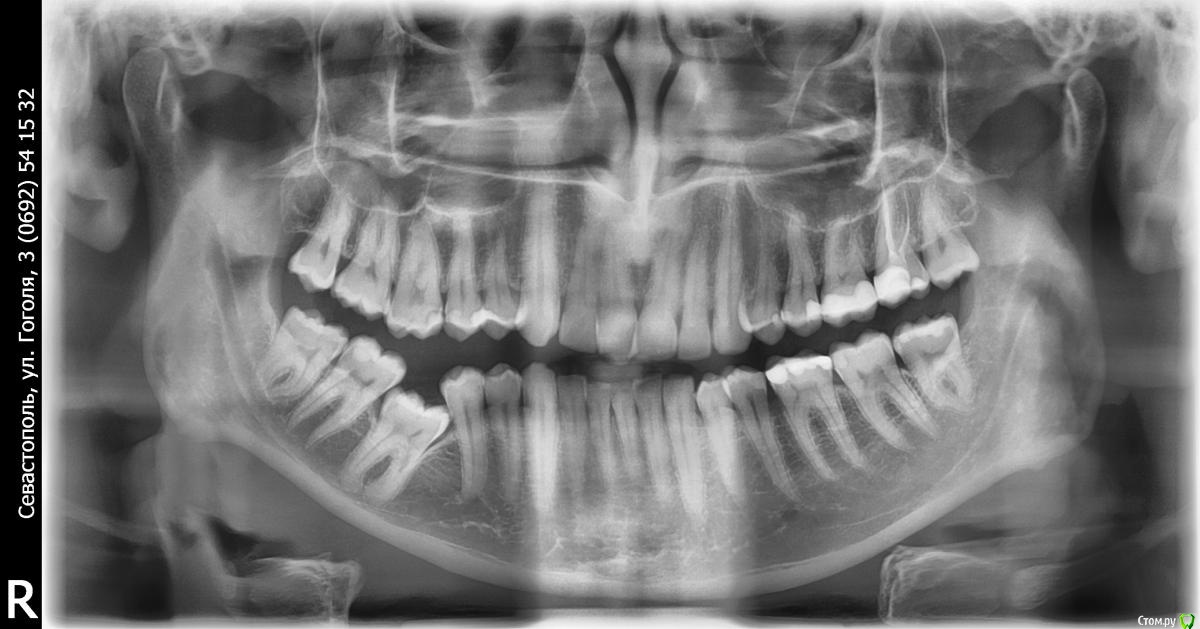

Tenpa Опубликовано 4 марта, 2021 Поделиться Опубликовано 4 марта, 2021 (изменено) Добрый день. 31 год, нижняя 6-ка зажата между 5 и 7. Как лучше исправить? удалять 8 ку и вытаскивать 6-й зуб? Изменено 4 марта, 2021 пользователем Tenpa Ссылка на комментарий

annda Опубликовано 7 марта, 2021 Поделиться Опубликовано 7 марта, 2021 А что ортодонты говорят?У оставшихся зубов может не хватить опоры для того, чтобы вытащить 6ку с кривыми сформированными корнями. Ладно, хоть анкилоза, похоже, нет. И то , не 100 процентов. Ссылка на комментарий

red_butler Опубликовано 7 марта, 2021 Поделиться Опубликовано 7 марта, 2021 Ладно, хоть анкилоза, похоже, нет. И то , не 100 процентов. похоже есть Ссылка на комментарий